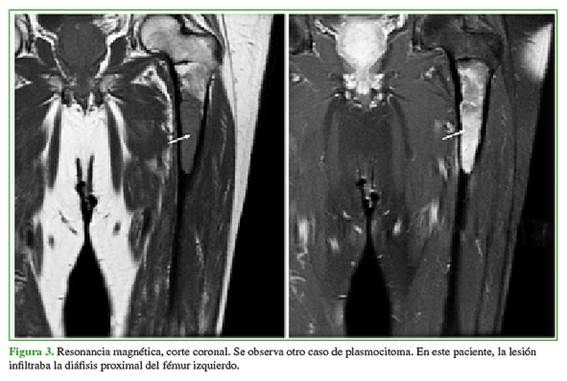

El plasmocitoma representa la neoplasia de células plasmáticas solitaria que puede progresar a MM (Figuras 2 y 3).